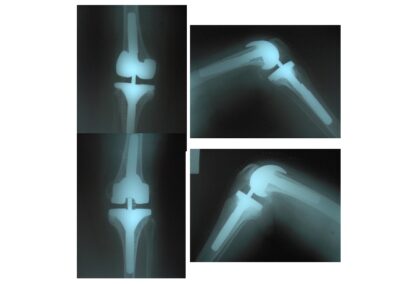

Hip and Knee ProsthesisDec 30, 2021 | Case ExamplesKnee Prosthesis Revisions Total Knee Prosthesis Unikondiler